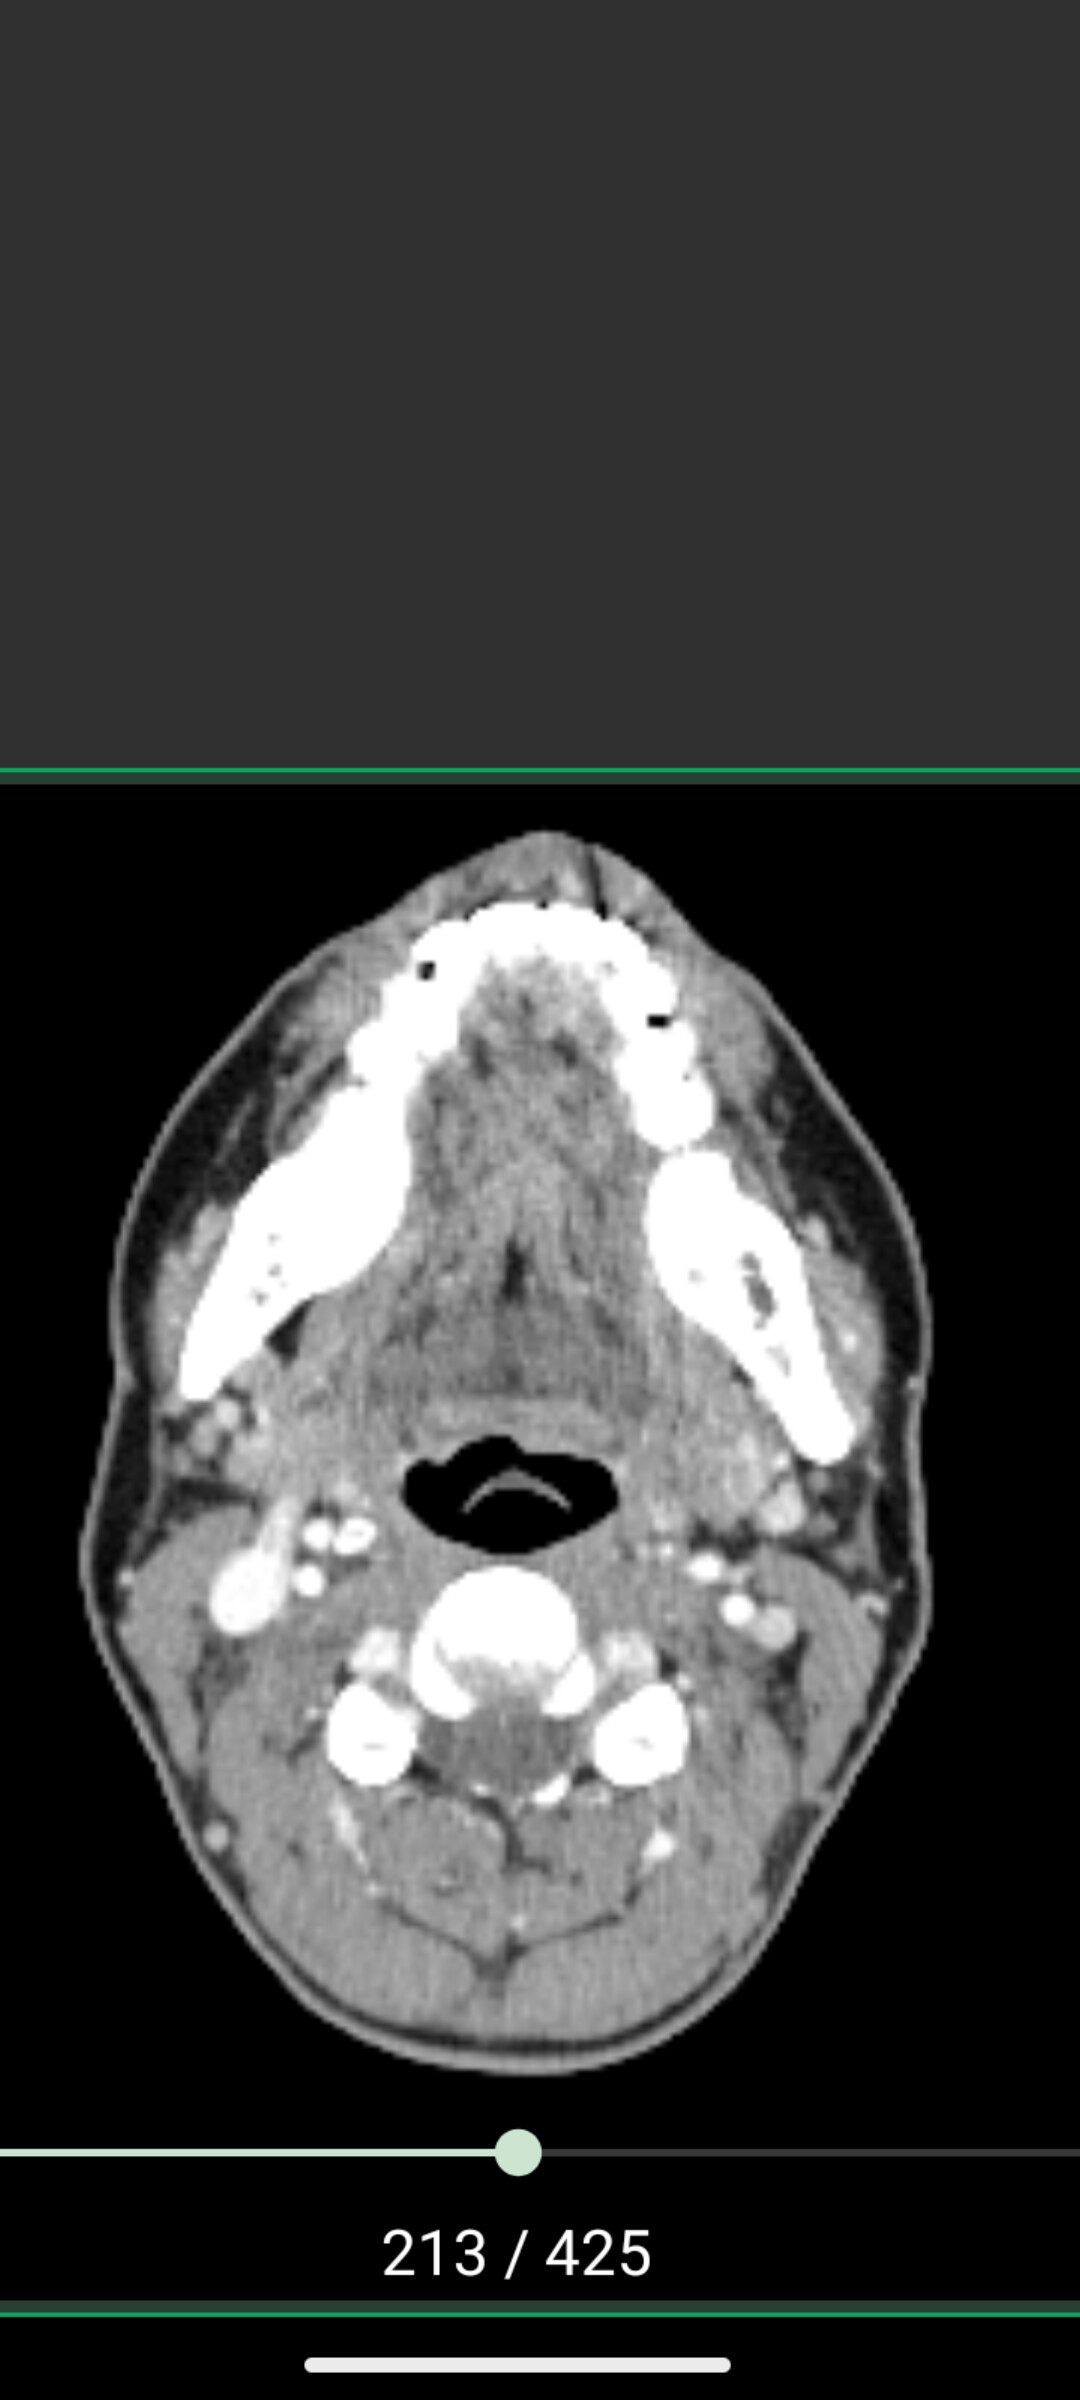

@Max330 this axial slice is perfect.

Pardon my language, but holy crap you might have the tightest space between a styloid and C1 that I’ve ever seen. Your LEFT styloid is so jammed up against your C1 transverse process that there isnt even an IJV to be seen. Probably so squished it doesn’t have contrast in it. Your right IJV is also compressed (not nearly as bad in comparison). IJV compression causes symptoms like pressure headaches, eye pressure, brain fog, memory difficulties, ear fullness, and dizziness (leading to balance issues). Your vagus nerves run between the IJVs and C1, which means they are probably compressed too. Vagus nerve compression can result in acid reflux, digestive issues, fight or flight response and HR and BP issues. I suggest a pillow wedge to sleep if you don’t already have one. Will help the IJVs drain with your head above your heart over night. A styloid-C1 distance in a healthy individual is about 9mm. I’d be surprised if you have half a mm on your left side.

I think with this knowledge you certainly should become 100% sure whether the surgeon plans to cut the styloid above the level of C1. You definitely need it trimmed higher up. I’ve never been more certain about something over the past few months on this forum. I really think your CCI-like symptoms will improve with styloidectomy. I think your right styloid could be removed too, but your left is definitely priority.

Here’s my Styloid-C1 distances to compare. And here’s what a healthy distance and IJVs should look like.

I agree with @TML about the space between the styloid & C1 process, it’s tiny! It would be ideal if you could discuss this with your surgeon & see how high he can remove the styloid to, but if he can’t take any more off, realistically what options do you have? It doesn’t seem possible (from what another Scottish member has said) that you could be referred to England, & options are very limited here too…unless you had plenty of money and could have it done privately with Mr Axon in Cambridge, which I presume isn’t an option? :worried:

@Max330 Good plan. Based on the axial slice, your right IJV is slightly compressed bur the styloid is not a culprit (it appears well clear of your right IJV) - so I think your right side could probably stay as is. Your left is definitely beating you up though.